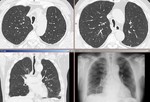

[画像メモ]マイコプラズマ肺炎(自分のノートより) 2010-06-14

[画像メモ]両側の浸潤影を呈する「肺炎」(自分のノートより) 2010-06-13